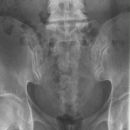

ISG p.-a.

Es wurden keine Bilder gefunden.

Technik

• FDA: 100 cm

• Ausgangsformat: 24/30 quer

• mit Raster

• Röhrenkippung 10 ° cranio-caudal

Lagerung

Bauchlage, Beine gestreckt

Zentralstrahl

Längsstrahl: Medianebene

Einblendung

oberes Licht 1 QF über Beckenkamm,

seitlich ca. 20 cm

Anmerkung

FDA ist 1,00 m, damit gehen auf Grund der Divergenz die Strahlen senkrecht durch die Fugen. Bei bauchigen Patienten etwas, am besten einen 45° Keil, unter das Becken legen, damit die ISG parallel zum Film stehen.

Qualitätskriterien

Symmetrische Darstellung des ventralen und des dorsalen unteren Anteils der Iliosakralgelenke